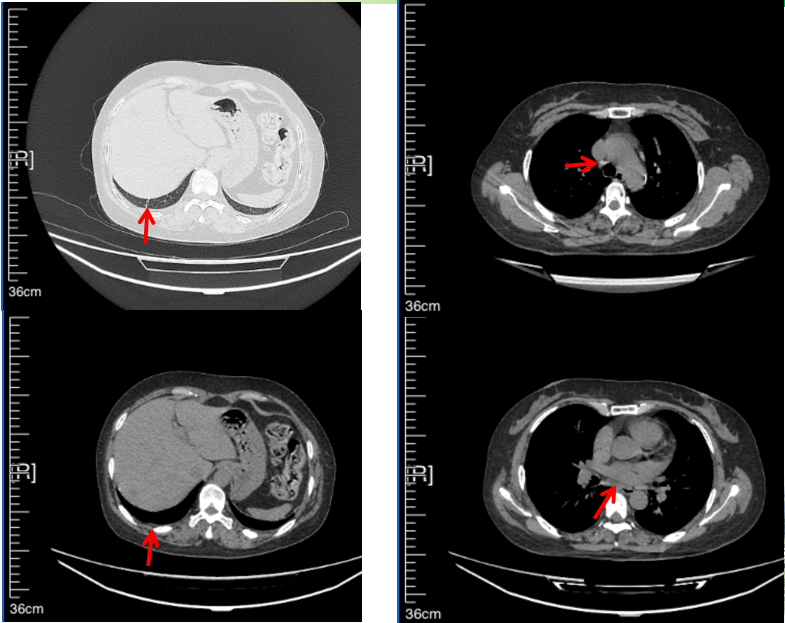

2016年1月复查CT提示支气管截断可见新发小结节,一线治疗采用培美曲塞+DDP方案化疗4周期(培美曲塞3.36,DDP 480mg)。化疗后复查胸部CT:右肺见不规则结节样影,最大层面大小约19mm*8mm,较前比较明显增大,疗效评估PD。2017.3-2017.4予单药多西他赛化疗3周期,疗效评估SD。2018年5月末复查CT提示结节较前增大,评效为PD,2018年6-10月予多西他赛+CBP化疗4周期,疗效评估SD。2022年5月患者出现活动后气短,复查胸部CT示右肺膨胀不良;右侧胸腔积液增多。胸腔积液包埋病理示符合肺腺癌细胞。行NGS基因检测:EML4:exon13-ALK:exon20融合。PD-L1(克隆号22C3)TPS<1%。

临床诊断:右肺上叶恶性肿瘤rT0N0M1a IVA期(第9版分期);恶性胸腔积液。

诊疗经过:2022年5月始口服克唑替尼3个月,出现肝功能异常(DILI 2级伴临床症状),改用恩沙替尼靶向治疗至今,目前评效为维持PR。恩沙替尼应用期间出现轻度肝功能异常(DILI 1级),对症处理后好转。截止目前PFS 33个月。

2018.07

2022.05

2022.08

2023.05

2024.12

56岁,女性,无吸烟史饮酒史,既往体健。2023年02月患者体检发现肺占位性病变,胸部增强CT:右肺下叶后基底段结节;右侧锁骨上及纵隔内多发淋巴结肿大。PET-CT:右肺下叶周围型肺癌可能性大;1R、2L、3P、4R、4L及7组淋巴结转移可能性大。2023年02月就诊于本院胸外科行超声胃镜下纵隔肿物穿刺活检术,病理:结合免疫组化,符合肺腺癌。行NGS基因检测:EML4:exon20-ALK:exon20融合。PD-L1(克隆号22C3)TPS=55%。

临床诊断:右肺下叶恶性肿瘤cT1bN3M0,IIIB(第9版分期),纵隔淋巴结继发恶性肿瘤,锁骨上淋巴肿继发恶性肿瘤

治疗经过:2023年3月27日始行恩沙替尼靶向治疗至今,最佳疗效为PR,末次评效为维持PR。期间出现轻度肝功能异常(DILI 1级),对症处理后好转。截止目前PFS为26个月。

2023年2月20日基线检查

2024年6月复查PR(最佳疗效)

2024年12月复查维持PR

2025年3月复查维持PR